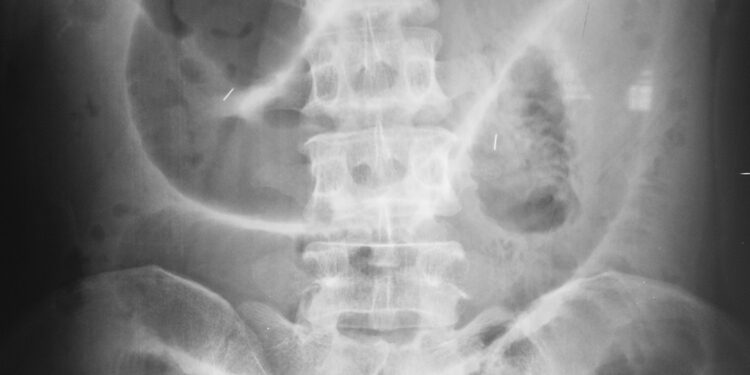

Neretai Meckelio divertikulas aptinkamas netyčia, atliekant kitus pilvo organų tyrimus dėl visai kitų priežasčių. Kiti žmonės apie jį sužino tik pradėjus kamuoti simptomams, kuriuos gali būti sunku susieti būtent su šia būkle – ypač suaugusiems, kurie iki tol niekuo nesiskundė.

- Meckelio scintigrafija. Tai radioizotopinis tyrimas, padedantis aptikti ektopinio skrandžio audinio židinius divertikule. Į veną suleidžiama nedidelė, visiškai saugi radioaktyvios medžiagos dozė, o viskas stebima specialia kamera.

- Mezenterinė angiografija. Šis kraujotakos tyrimas parodo, ar į divertikulą teka atskira kraujagyslė, gali padėti nustatyti jo vietą ar pamatyti kraujavimo židinį. Ne kiekvienu atveju kraujagyslių tinklas atrodo pakitęs, todėl ne visada šis metodas informatyvus.